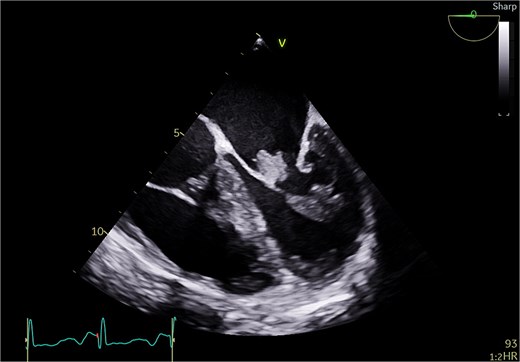

She underwent sternotomy with mechanical mitral valve replacement (MVR) and tricuspid valve (TV) repair with LA appendage clip and removal of loop recorder. Intra-operatively, there was extensive destruction of posterior leaflet and tissue damage with no dilatation of annulus (Fig. 3). Anterior leaflet was thickened. Valve was excised and sent to pathology and microbiology. Post-operative TEE showed well-functioning mitral valve with no para valvular leak and mild TR. Her post-operative course was uneventful. Cultures were sterile and histology showed chronic inflammation with fibrosis, myxoid degeneration, and calcification. Irregular tan Brown nodules were seen with areas of calcification on the mitral valve. Patient was commenced on Aspirin and warfarin. As the appearance of mitral valve was highly suggestive of LSE, the rheumatology service was consulted to rule out SLE both clinically and biochemically. Table 1 is a summary of her lab tests that confirmed the diagnosis of SLE. Pre-discharge TTE showed well-functioning mitral valve and mild TR. She was discharged home day 11 post-op with therapeutic INR. At 1 year follow up, patient was well with no strokes or bleeding.